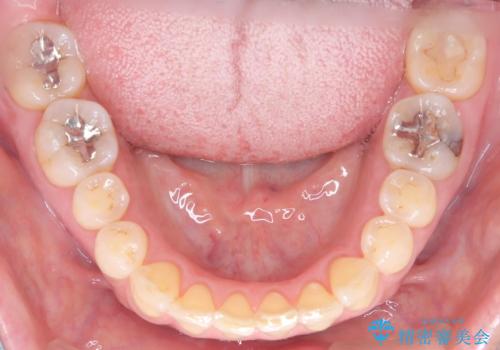

ワイヤー矯正ならではの確実な歯のコントロールにより、当初の計画通り約1年という短い期間で、前歯のガタつきが解消。見た目が美しく整っただけでなく、清掃しやすい機能的な歯並びを獲得していただけました。

スペース確保のために、まず奥歯全体をわずかに後方へ動かす遠心移動を実施し、前歯を並べるためのスペースを確保。さらに、安全性に配慮しながら歯の側面をわずかに削るIPRを併用し、デコボコを解消しました。